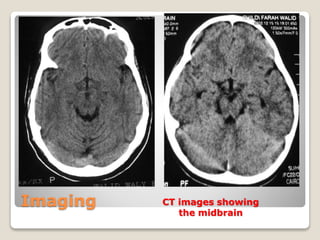

Imaging CT images showing

Imaging CT with contrast images